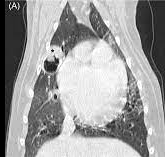

이 연구자는 CT 촬영도 진행하는 등 빠지지 않는 완전 검사 자료를 확보하여 진단의 깊이를 더했다. 훌륭하다.

즉, bullar로 치부하지 말고 CT 촬영을 통해 종괴 가능성 평가를 할 필요가 있다는 것을 실증한 논문임과 동시에